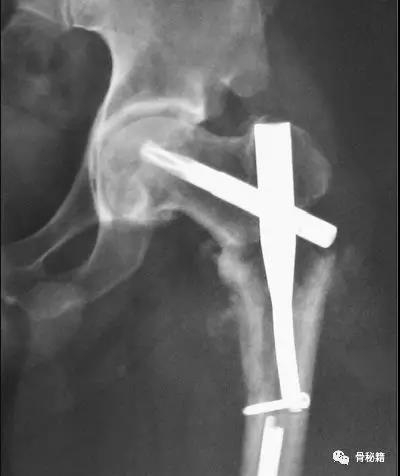

来一个比较有意思的病例大家讨论:

一个双膦酸盐治疗5年的患者粗隆下非典型骨折

采用了髓内钉固定,术后一年内固定失效

更换了DCS+植骨固定,术后四个月又发现了内固定失效再次更换了更长的DCS

这次的固定能成功吗?